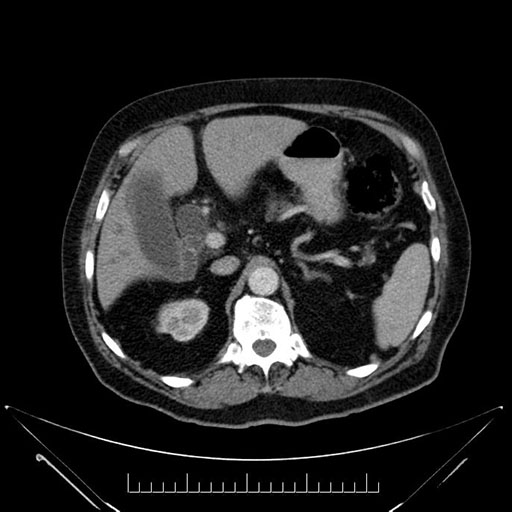

Axial - stented